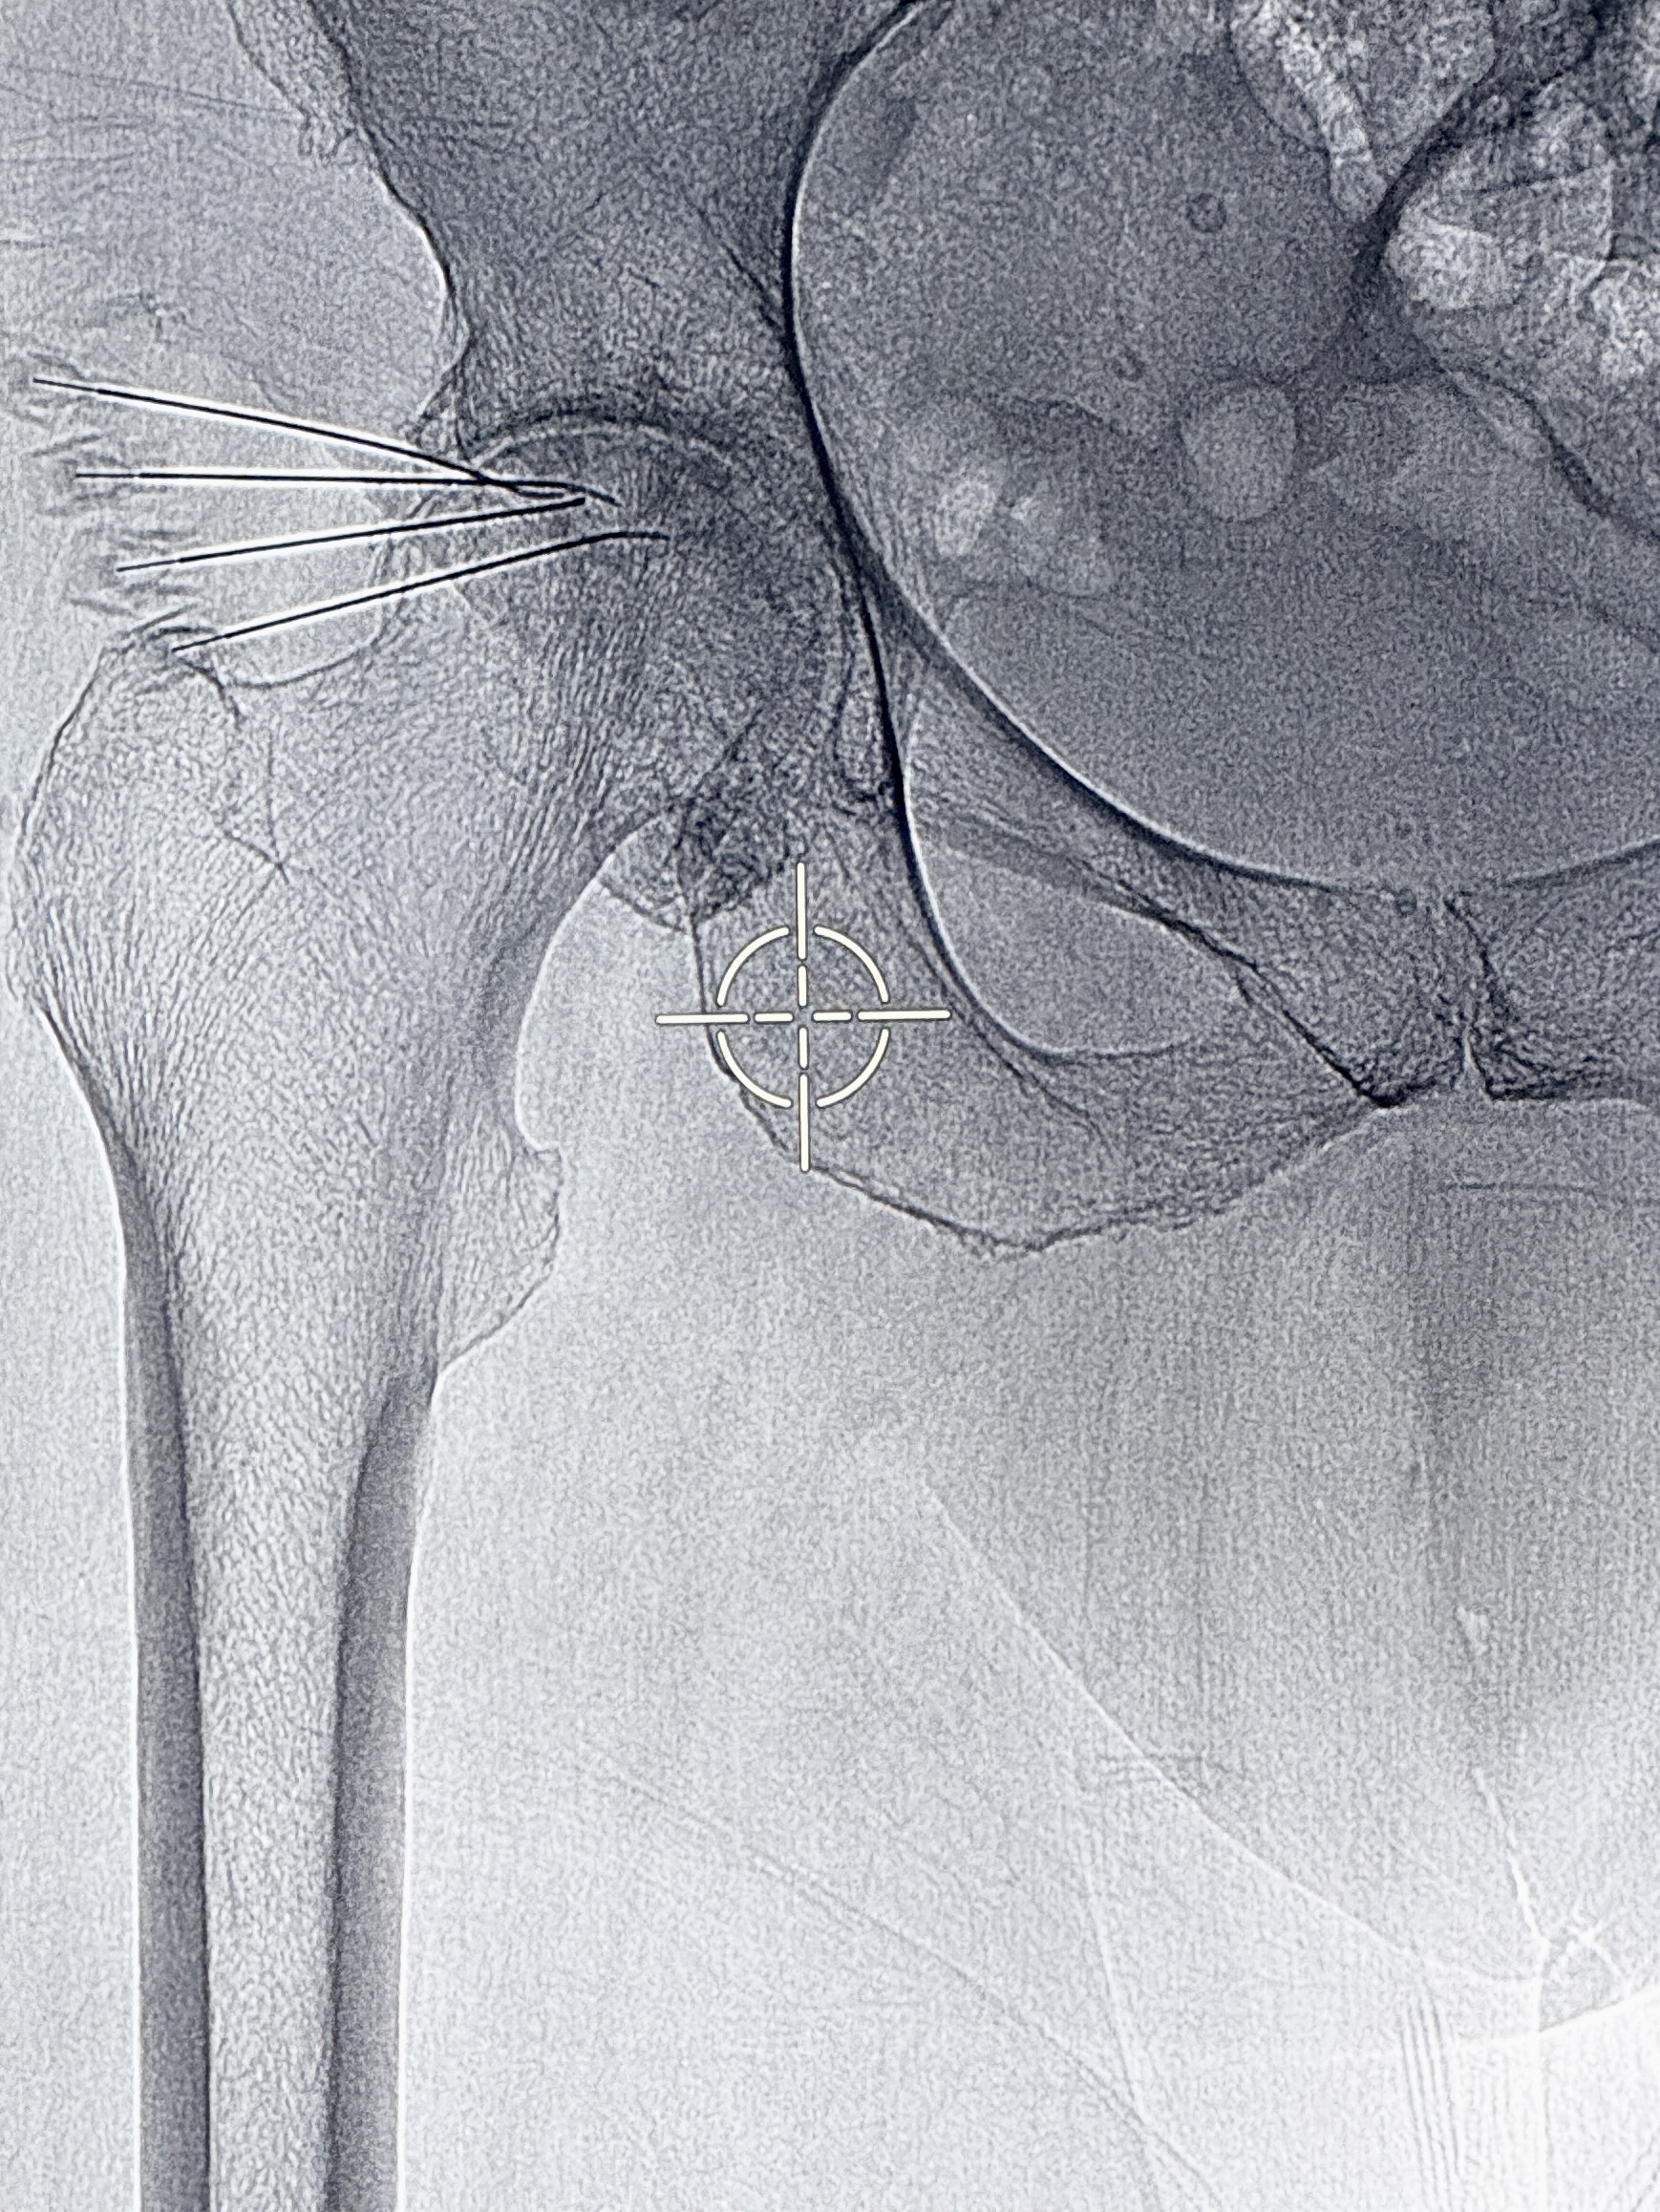

Nuestro objetivo es mejorar tu calidad de vida y acompañarte en cada paso con tratamientos mínimamente invasivos

Anestesiólogo con Subespecialidad en Algología Intervencionista con más de 10 años de experiencia en el tratamiento y alivio del dolor. Su enfoque combina profesionalismo, tecnología de vanguardia y un equipo multidisciplinario altamente capacitado para brindar atención excepcional e integral a cada paciente, mejorando su calidad de vida.